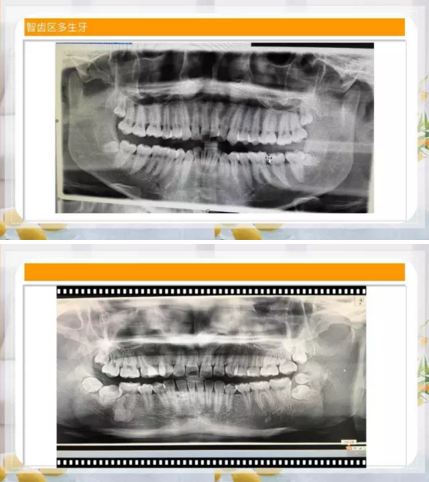

智齒區(qū)多生牙

10.png

11.png